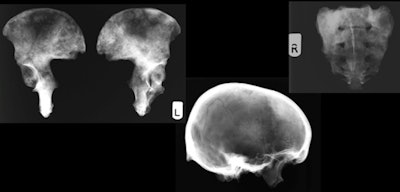

Osteological analysis was carried out on the 213 adult skeletons a few years before radiological analysis took place. For 189 individuals, x-rays of the crania, humeri, pelvises, femora, and tibiae were taken in situ with a portable x-ray machine, and examined. These bones were selected because they were most likely to show evidence of a wide range of pathologies and were present for all skeletons, according to the authors. It was not possible to x-ray 24 skeletons due to postmortem decay.

So how did the individuals found in the crypt live and die? In general, the population of 19th century London was more malnourished than Western European populations today -- many of the St. Bride's skeletons showed evidence of rickets and there were also a few cases of tertiary syphilis. Notably, a subset of the individuals lived into their 70s, and did so seemingly in relatively good health. In at least two cases, evidence of metastatic cancer was noted on the skeletons. X-rays helped to characterize the extent of these lesions.